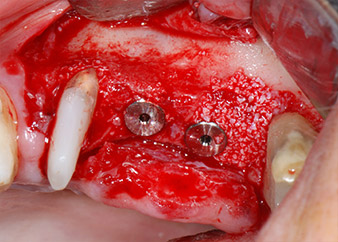

Преди поставянето на импланта, инфектираната тъкан е отстранена от алвеоларната кост в имплантното ложе и около зъба-абатмънт с накрайник, проектиран за оформяне на костта и събиране на костни блокове (Piezomed, накрайник B5) (Фиг. 6 и 7).

Имплантологичното ложе е подготвено в позиции 25 и 26 с ротиращи инструменти, използвайки обратен наконечник 20:1 с усъвършенстван и мощен имплантологичен мотор (Implantmed, W&H) (Фиг. 8).

Следващата препарация близо до синуса отново е извършена с пиезохирургичен накрайник (Piezomed, накрайник S2).

Преди поставянето на имплант, и последвалото потвърждение за непокътната Шнайдерова мембрана (Фиг. 9), вътрешният синус е повдигнат и в двете места на имплантите с помощта на ксеногенен костозаместващ материал (Bio-Oss, Geistlich Biomaterials) (Фиг. 10).